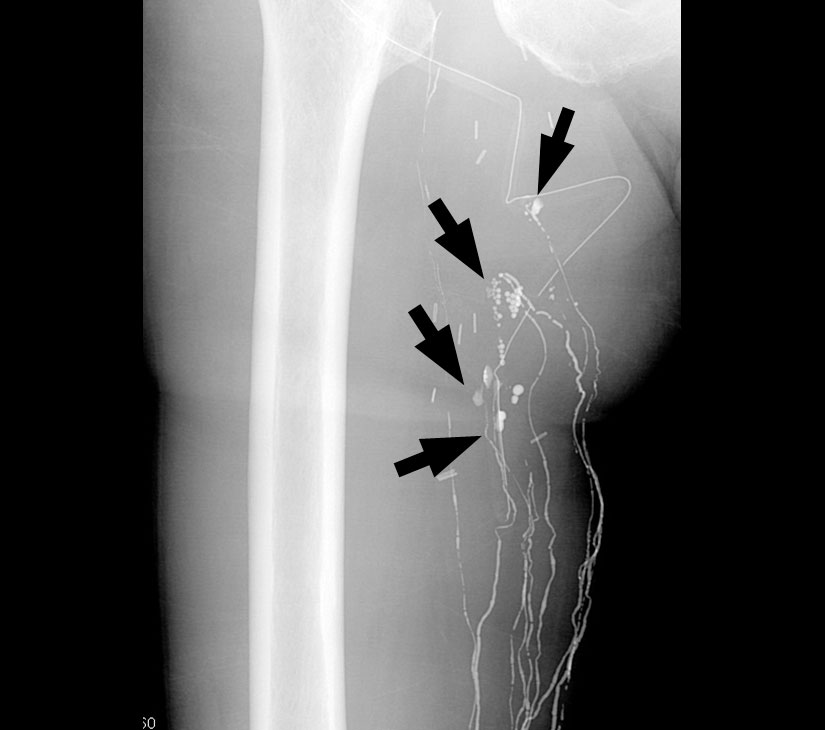

- リンパ管造影における投与部位(例)

- Ⓐ足背(足の甲)に切開を入れて、リンパ管を穿刺して本剤を緩徐に注入する。

- 本剤を皮膚直下の末梢リンパ管内に注入する。用量はヨード化ケシ油脂肪酸エチルエステルとして、通常、上腕片側 5~ 6 mL、下肢片側10mLである。注入速度は毎分0.3~0.5mL 程度が望ましい。